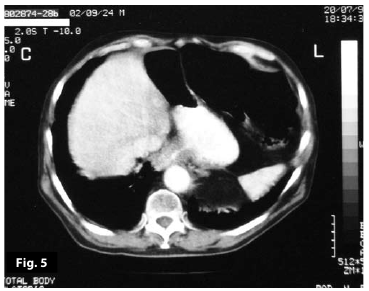

Figure5

Figure6

Figure5-6